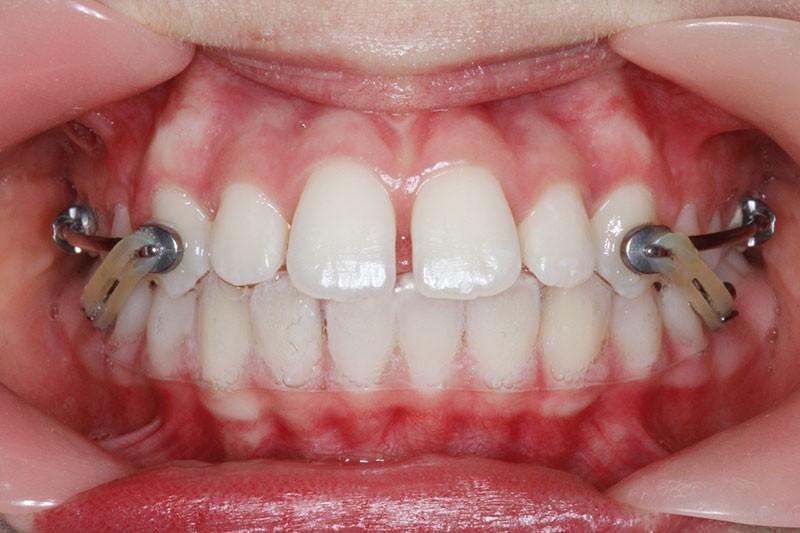

Il a été décidé de mettre en place un système de correction de la classe II “Motion Classe II Carriere” composé de bras latéraux reliant canine et molaire et d’élastiques de classe II ancrés sur des tubes molaires sur 36 et 46 et une gouttière thermoformée portée en permanence. sAprès dérotation des 16 et 26, recul des secteurs latéraux et libération de la croissance mandibulaire nous mettrons en place un système multiattache autoligaturant passif Carriere SLX 022×028 avec la séquence d’arcs suivante :

1re phase : le Motion Appliance Carriere

Afin d’obtenir la correction de la classe II, nous avons fait porter pendant 3 mois une mécanique d’élastiques intermaxillaires, jour et nuit, avec la séquence suivante (fig. 4):

1er mois : élastiques 6oz. ¼”

2e mois et mois suivants : 8 oz. 3/16”